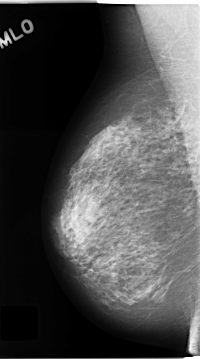

C_0144_1.RIGHT_MLO

ics_version 1.0

filename C-0144-1

DATE_OF_STUDY 3 7 1995

PATIENT_AGE 74

FILM_TYPE REGULAR

DENSITY 3

DATE_DIGITIZED 18 2 1998

DIGITIZER LUMISYS LASER

RIGHT_MLO LINES 4664 PIXELS_PER_LINE 2592 BITS_PER_PIXEL 12 RESOLUTION 50 NON_OVERLAY